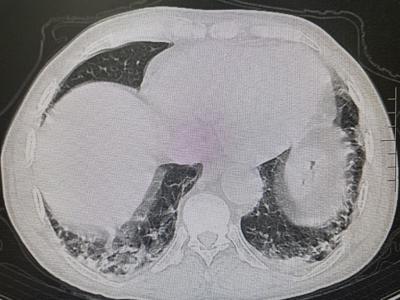

時間回到2020年元月,風濕免疫科收住一位71歲的老年男性患者,四肢肌肉無力已經5月余伴反復發(fā)熱1月,雙上肢不能抬舉,雙下肢不能下蹲站起,行走困難,面頰部、眶周、雙手背出現(xiàn)鮮紅色皮疹,腫脹明顯,伴有明顯胸悶、氣短,進食及吞咽困難,全身多關節(jié)疼痛。該患者先后在當?shù)鼐驮\兩家大型三甲醫(yī)院的多個科室,因為診斷不明,始終治療無效。歷經周折來到風濕免疫科后,科室團隊經過綜合評估診斷為“皮肌炎并重度肺間質病變”。

(2020年1月 肺部HRCT)

經近2年的門診規(guī)范化診療,病情完全得以控制并處于持續(xù)的穩(wěn)定狀態(tài)。近期復查肺部HRCT示間質性炎癥已完全吸收,肺功能檢測也基本正常,患者皮膚、肌肉、關節(jié)癥狀全部消除,現(xiàn)日常生活已恢復常態(tài),從事以前一樣的勞作。為此,老人及家屬充滿了感激之情。

(2021年12月 肺部HRCT)